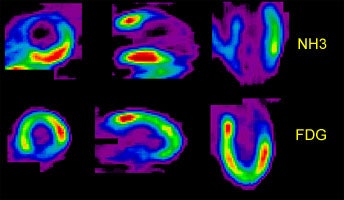

|

.Myocardial PET FDG imaging: |

|

Myocardial scar: The patient below was being considered for coronary bypass surgery. A rest thallium exam demonstrated findings consistent with an apical and anterior wall scar. FDG PET imaging was requested to confirm that the patient was not a surgical candidate. The PET scan demonstrated a severe apical and anterior wall metabolic defect with less than 50% of peak myocardial activity corresponding to the thallium scan abnormality. The finding was consistent with prior apical and anterior wall infarct. |